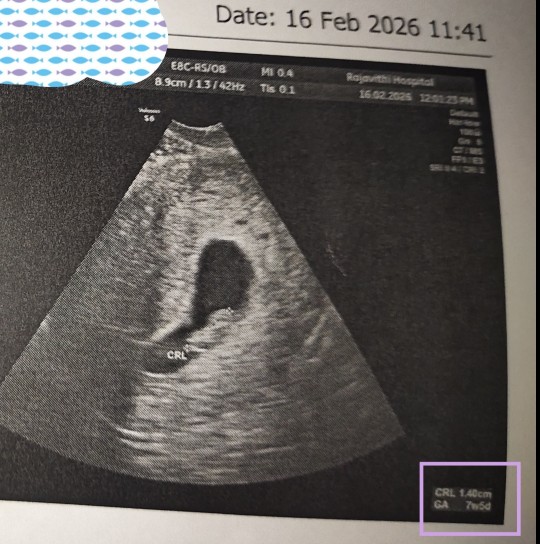

ท้อง7วีค3วันเจอแต่ถุงมีโอกาสจะเจอน้องมั้ยคะ แม่ๆเจอเจ้าจิ๋วกันกี่วีคคะ🙏💓

ท้องแรกเจอทุกอย่างตอน6+4 ท้อง2เจอทุกอย่างตอน7+3

ถ้า7วีคน้องยังจิ๋วอยู่มากตามภาพเลยตอนแรกก็ไม่เจอหมอซาวหมุนหาอยู่นานเลยกว่าจะเจอค่ะ หลายๆคนจะยังไม่เจอช่วงอายุนี้ก็มีค่ะ รออีกสัก1-2วีคนะ